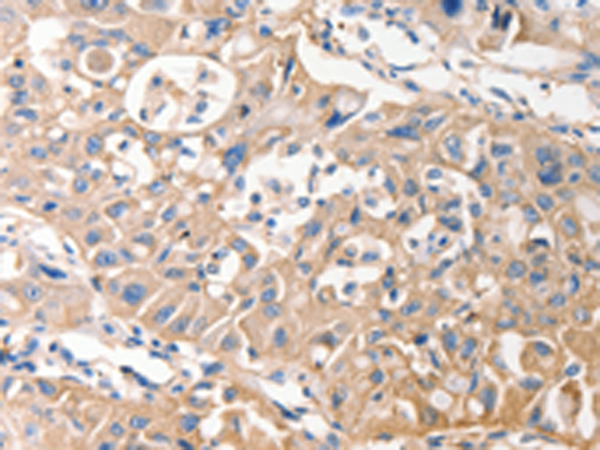

IHC positive control: |

Human lung cancer and Human esophagus cancer |

IHC Recommend dilution: |

25-100 |